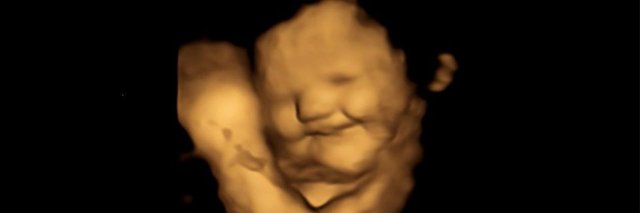

Araştırmacılar, hamile kadınlara önce havuç sonra lahana kapsülü verdi ve bebeklerin tepkilerini 4D ultrasonla izledi.

Havuç aromasına maruz kalan bebekler daha fazla “kahkaha surat” tepkileri verirken, lahana aromasına maruz kalanlar daha fazla “ağlayan yüz” tepkileri gösterdi.